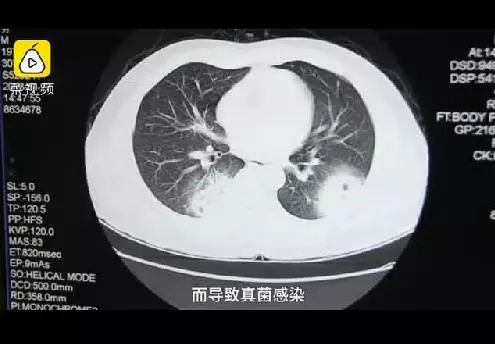

还记得去年那位福建漳州的大叔么

经常脱了鞋闻臭袜子

最后得了肺炎